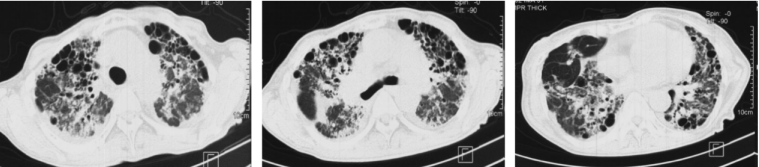

9年前(2014年),患者呼吸困难逐渐加重,不能爬山或剧烈活动,爬2层楼梯后自觉憋气,伴咳嗽、咳痰加重,晨起为著,无发热、咯血、胸痛。再次就诊于北京某三甲医院,动脉血气分析(2014-08-27,未吸氧):pH 7.41,PaCO2 35.5 mmHg,PaO2 49.1 mmHgSaO2 82.4%;胸部CT示:双肺野可见弥漫性斑片状高密度影,部分呈铺路石样改变(图2);肺功能示:限制性通气功能障碍伴弥散功能减低(表1)2014年9月22日行全麻下全肺灌洗术,双肺均灌洗生理盐水10000 ml,分别回收淘米水样灌洗液10300 ml(左肺)及10750 ml(右肺),术后呼吸困难症状好转不明显,鼻导管吸氧5 L/min时,指脉氧饱和度可维持95%左右。出院后规律门诊随访,呼吸困难症状未减轻,需氧疗,加用粒细胞-巨噬细胞集落刺激因子(GM-CSF)150 μg 2次/日(用1周、停1周)雾化吸入治疗数月,患者症状略改善。

图片

2  患者2014年9月胸部CT